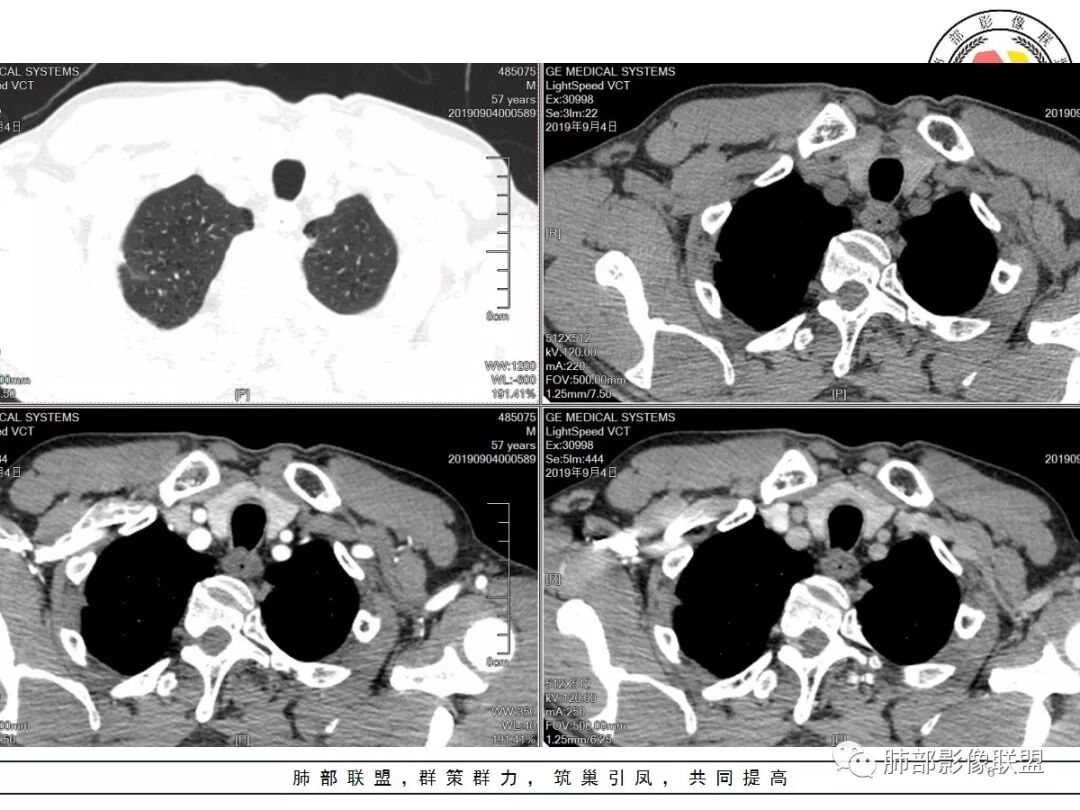

男,57岁,因“体检发现右上肺占位”入院。凝血常规、血常规、肾功能等均未见明显异常。

CT值:

平扫  18                          动脉期  28                      静脉期 41

重建

双肺尖斑片状影及结节影,边缘平直为主,边缘可见胸膜牵拉,考虑结核,鉴别诊断腺癌,本病特点,多灶性,多态性,胸膜牵拉线纤细。

右上肺病灶,边缘平直,有卫星灶,强化不明显,考虑结核可能大

结核。右上肺结节密度均匀轻度强化,结节边缘清晰有小分叶,周围细长软毛刺,有卫星灶。左上肺近纵隔类似片状结节。

右肺尖结节边缘可见卫星灶,结节边缘平直凹陷、长毛刺,外观上有炎性结节的特点

增强扫描右肺尖结节强化不明确,但左肺尖后段结节出现了典型的环形强化

右肺结节影,边缘平直,有长索条与胸膜相连,左肺尖有条片状密度增高影,边缘清晰。左肺门斑点状钙化。考虑结核,老年人右肺上叶警惕瘢痕癌,建议复查。

右肺上叶结节灶,边缘膨隆,有毛刺,胸膜牵拉,轻度强化,左肺上叶结节灶环形强化,左肺考虑结核,右肺结节灶,不排除疤痕癌。

两肺上叶结节影,右肺结节边缘清晰,平直,有胸模牵拉,有卫星灶,强化不明显,左肺结节周边强化,两肺门淋巴结肿大,整体考虑结核。

右肺上叶结节,边缘部分膨隆,毛刺,内部有强化增粗血管影,边缘有空泡,胸膜有牵拉,考虑腺癌。鉴别结核。

右肺尖结节边缘可见分叶,结节边缘有毛刺,但左肺尖后段结节出现了典型的环形强化,考虑炎性病变,右上肺结节鉴别腺癌。还有患者食管上段壁明显增厚。

中年男性,查体发现,右肺肺上叶结节影,边缘平直收缩,周围有软毛刺,有胸膜牵拉,左肺上叶靠近纵隔不规则结节影,边缘平直内收,内有坏死。考虑良性病变可能性大,肺结核。鉴别肺癌合并结核。

中老年男性,体检发现双肺尖结节,边缘长索条,邻近胸膜粘连,病灶收缩力不太强,右肺尖病变周围少许卫星灶,增强后环形强化表现,首先考虑结核,治疗后复查

两上肺(右尖左尖后)都有小结节影,右肺尖结节边缘可见卫星灶,结节边缘平直凹陷、长毛刺,部分膨隆,增强扫描右肺尖结节强化不明确;左肺尖后段结节边缘平直凹陷,增强见环形强化。考虑结核可能性大,右上肺注意鉴别腺癌。

右上肺结节影,有平直收缩有膨隆,有长短毛刺,胸膜牵拉,增强扫描强化不明显或轻度强化,左上肺少许条索斑片状影,强化无特殊,纵隔肺门淋巴结钙化,肺气肿,肺大泡背景,老年男性,首先一元化都考虑结核,右肺上叶结节周围血管稍增粗,需要警惕合并肺癌。

男,57岁;图像质量好,1.25*10层=12.5mm,两个病灶,形态奇特,毛刺长,强化静脉期最高,增强稍微中心密度低一些,肺尖部位;

诊断:结核(多灶,2;多态,中心低、边界稍高);部分,肺尖;毛刺,长,非真正毛刺。

老年男性,体检发现右上尖段及左上尖后段不规则结节影,右上尖段结节边缘长毛刺、似见卫星灶、局部胸膜牵拉,增强无明显强化。左上结节环形强化,考虑结核。老年男性,肺气肿背景,注意排除右上肺腺癌。

右肺上叶尖段结节,边缘平直收缩,周围有细长毛刺,有卫星灶,符合结核,但有静脉期轻度强化,结核应该没有强化,肺癌?

双肺尖结节 左肺边缘收缩 环形强化 右肺病灶上部边缘平直及长毛刺 下部分边缘膨隆及分叶 细短毛刺 好像有局灶强化 不除外结核基础上的瘢痕癌可能

倾向二元,左肺上叶病灶环形强化支持结核,右肺上叶结节平直、部分稍膨隆,胸膜牵拉征,部分毛刺粗短、支气管似乎边缘截断,临近小叶间隔增厚,延迟强化,密度似乎不均匀,内见小点状坏死,腺癌放前面,炎性放待排。